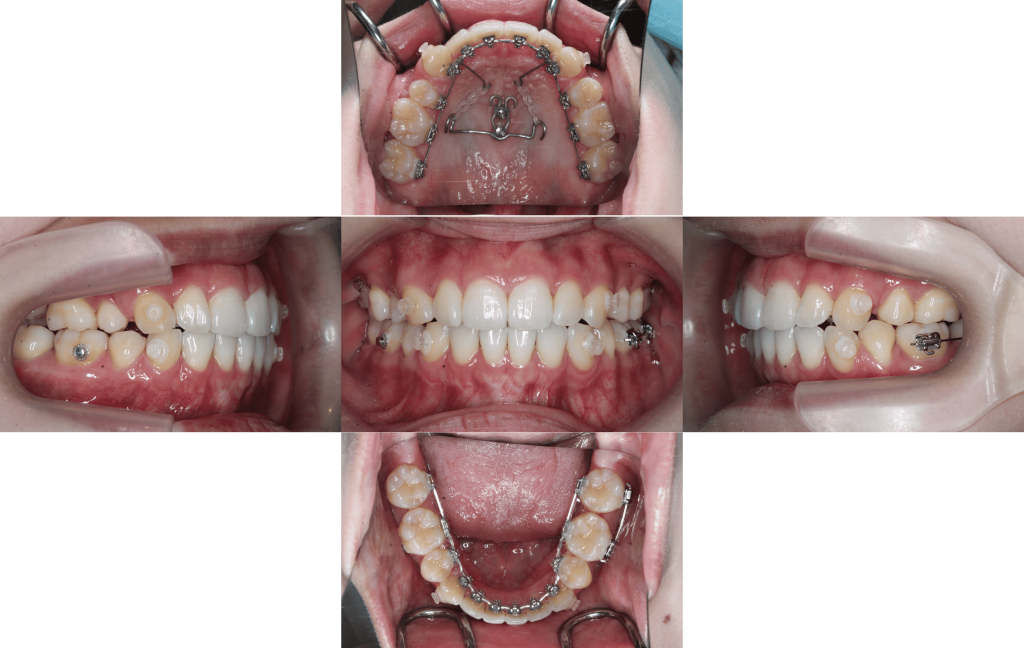

約1年経過